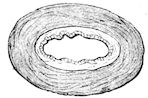

Fig. 8.—Transverse section through the middle region of the face in a pig suffering from osseous cachexia.

18In the final stages, the bones may be cut with a knife, and a time arrives when bony tissue seems completely to have disappeared; thus, as shown in Fig. 8 herewith, it was possible to cut the entire head of a pig into thin slices without the slightest difficulty. All parts of the head had been affected by the softening change.

From the chemical point of view, the diminution in mineral salts and in phosphate of calcium has long been recognised, but the degree of this change varies according to the phase. In human beings the proportions have been estimated as follows: Normal bone, 50 to 80 per cent. of phosphate of calcium; bone in persons suffering from osteomalacia, 5 to 20 per cent. of phosphate of calcium. The changes in the ossein have not been carefully studied. We only know that histologically the ossein becomes fibrillar, and that chemically it no longer retains its normal composition.